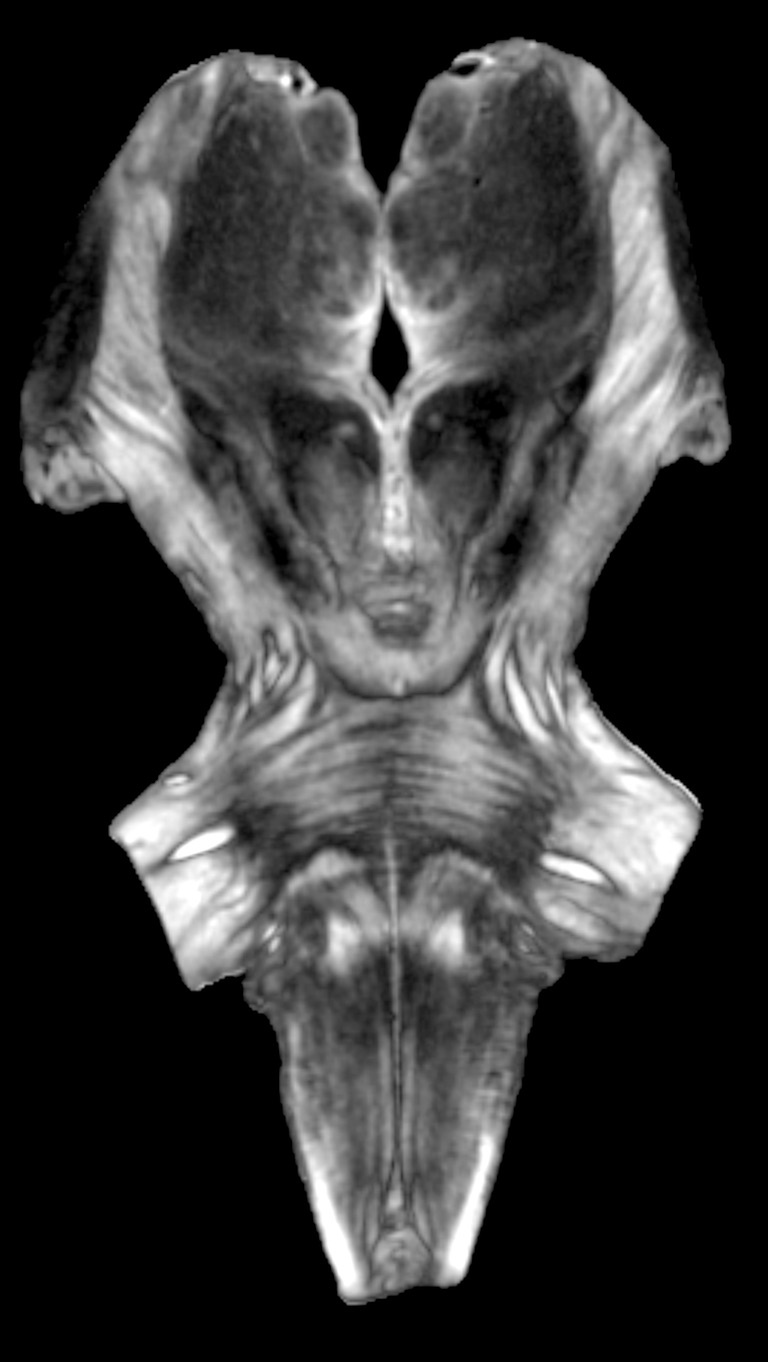

Demonculus: Image of a Postmortem Brainstem

McGovern Institute for Brain Research, MIT Department of Brain and Cognitive Sciences

This spooky, face-like image is from an MRI scan of a post mortem human brainstem and thalamus. I am investigating the human auditory system, particularly the subcortical components below the cerebral cortex. This system is difficult to study in normal human participants, in part because MRI isn’t high enough quality when we only have an hour or two to collect the MRI scan. Imaging a post mortem brain allows us to get much better resolution and image quality than we can get from a standard MRI with a living, breathing participant. Thus, we get much finer detail in a scan of a post mortem brain, meaning we can see brain structures and connectivity fibers much more clearly—some of which look like an illusory humanoid face!